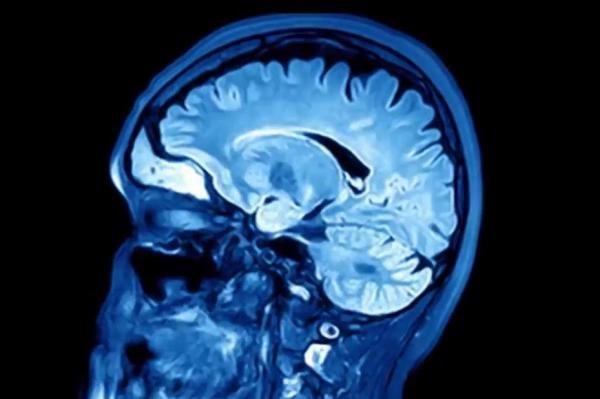

درحالیکه سکته مغزی با علائمی از قبیل احساس ضعف در دست ها یا مسائل گفتاری خود را نشان می دهد سکته خاموش تنها به وسیله اسکن مغزی قابل تشخیص است.

در این آنالیز جدید بیش از 1100 شرکت کننده میانسال از آمریکای شمالی، جنوبی، آسیا، نیوزیلند و اروپا حضور داشتند که تحت عمل جراحی غیر از ناحیه قلب قرار گرفته و در مدت 9 روز بعد از آنان اسکن مغزی گرفته شد. از هر 14 نفر یک بیمار دچار سکته خاموش بوده که نشان می دهد سالانه سه میلیون میانسال در دنیا پس از انجام جراحی دچار سکته خاموش می شوند.

به گزارش هلث دی نیوز، محققان کانادایی بر این باورند که سکته های خاموش در افراد 65 ساله و بالاتر که جراحی داشته اند شایع تر است. همچنین آنان این بیماران را برای مدت یک سال پس از انجام عمل جراحی تحت کنترل قرار داده و مشاهده کردند افرادی که دچار سکته خاموش شده اند نسبت به دیگران بیشتر در معرض زوال ذهنی بوده اند.